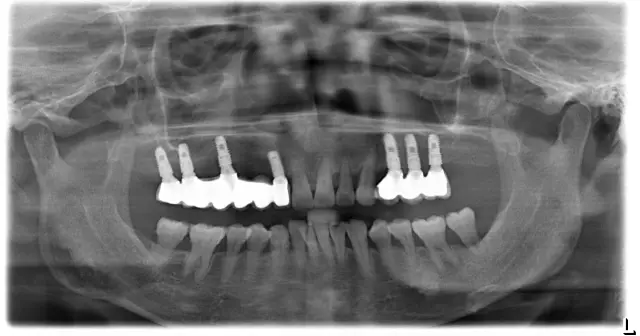

▲种植后

种牙之后让她有了很大的改变,听说是刚刚在山塘街拍完写真照赶过来的,点击语音,直接感受阿姨的分享。